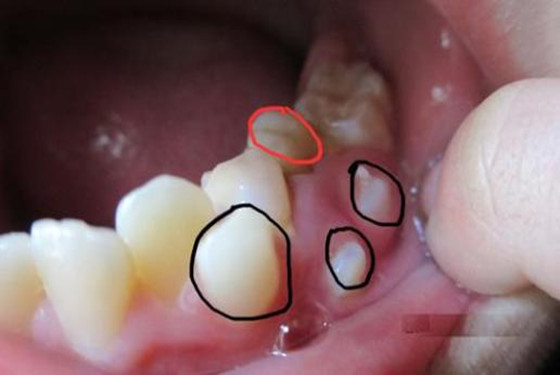

如果是新牙已经开始萌出,最好是带孩子去牙科拔掉,如果此时不拔出即将脱落的牙齿,反而会影响新牙的生长(长歪那是必然的)。如果孩子害怕拔牙的话,就让他吃一点稍硬的水果,比如苹果,梨子这类较为坚硬的食物,通常很容易把快要掉,但却还没有掉下来的牙齿给挤下来。如果不行,就只能找医生拔了。另外,要是牙齿腐烂了,需要牙医进行拔除或者填补治疗,这种情况妈妈千万不要试图自己拔掉腐烂的牙齿,那样会造成牙龈裂开或者形成脓肿的情况。